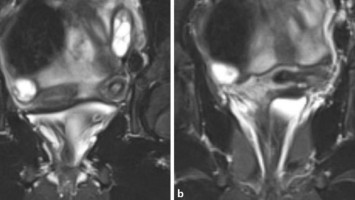

Urogenitale Fistel: So wurde die Patientin endlich beschwerdefrei

Eine 36-Jährige hat bereits mehrere abdominale Operationen hinter sich, um die bestehende Endometriose zu behandeln. Die daraus bedingte Urogenitalfistel und damit einhergehende totale Harninkontinenz konnten bislang nicht erfolgreich behandelt werden.